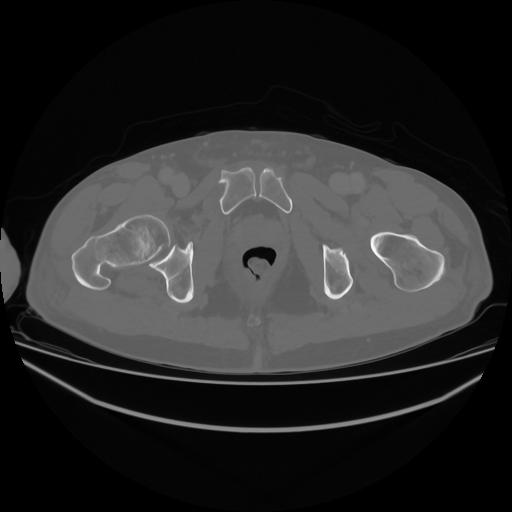

5 CUERPO,CE,Vol,1.0,CUERPO,,